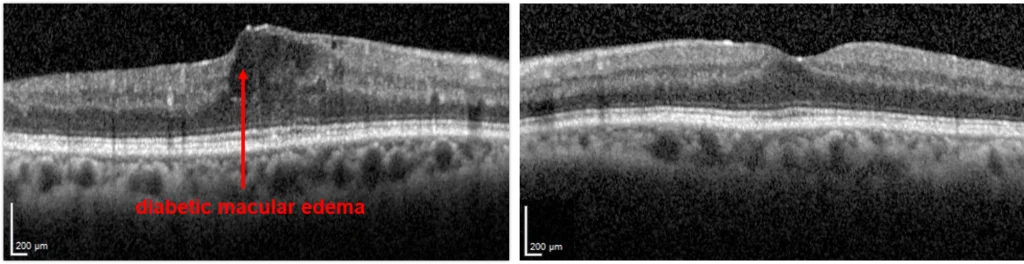

Diabetic Macular Edema (DME)

Patients with either NPDR or PDR may develop diabetic macular edema, otherwise known as swelling. Blood vessels damaged by diabetes are leaky, and the fluid that leaks from these vessels accumulate in the retina.

The macula is the centermost part of the retina, which is responsible for much of high quality vision. When diabetes causes swelling in the macula, one has “diabetic macular edema.”

In order to evaluate diabetic retinopathy, a doctor may perform tests such as dilated retinal examination and optical coherence tomography (a scan to look for swelling in the retina (DME). In some patients they may perform a fluorescein angiography or a b-scan ultrasound.